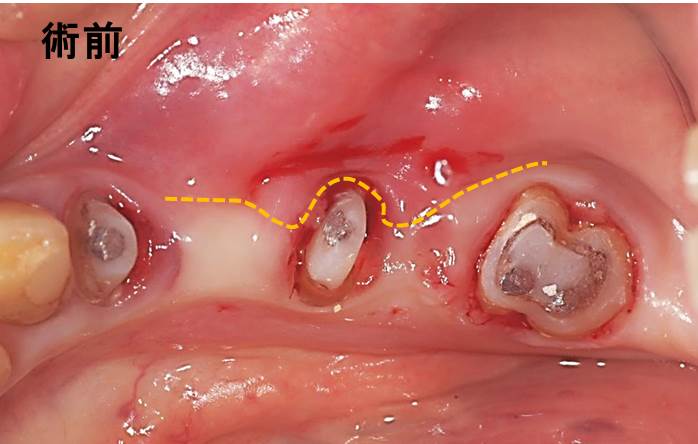

下写真のオレンジ線は、「動く歯茎」と「動かない歯茎」の境界線です。「動かない歯茎」が無く、「動く歯茎」が歯の周りを覆っています。